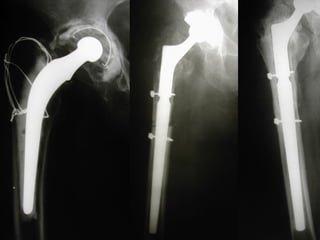

Paprosky 2B

F.U 5 aa